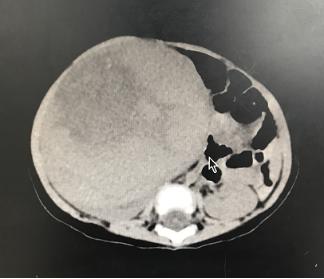

经过医院副院长林芃主任医师细心检查,茜茜的腹部可触摸到肿物,直径约10厘米,几乎占满了宝宝的肚子,考虑为左侧肾母细胞瘤。肿瘤还在继续生长,有破裂的可能,情况紧急,必须尽快进行手术治疗。随后,肿瘤外科医师团队认真为茜茜进行详细的术前检查,制定具体的治疗方案。

经过充分的术前准备,林芃主任医师在茜茜的左侧腹膜后发现大小约10.1cm×9.5cm×8.6cm,呈暗灰色的巨大肿物,肿瘤已经把左侧肾脏给“吃掉”了。由于瘤体、肾脏血管及输尿管错综复杂,切除肿瘤过程必须更加严谨和审慎,稍有不慎就极有可能损伤重要血管,引起大量出血。